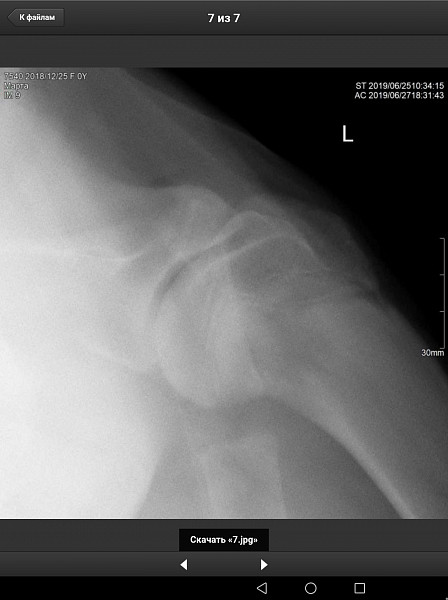

У нас немецкий дог, девочка, 6 месяцев, привита по возрасту. Поставлен диагноз Расслаивающий остеохондрит плечевого сустава (мышь плечевого сустава). Сказали, нужна операция по зачищению этого сустава. Как можно скорее.

Есть рентгеновский снимок. Прошу вас прокомментировать его, правильный ли диагноз? Как срочно нужно оперировать, если подтвердится диагноз? Какой период реабилитации? И, что нас ожидает в будущем, от чего могла развиться болезнь, наследственное это или нет, что делать, чтобы предупредить заболевание суставов других лап?

Здравствуйте. Судя по описываемым вами симптомам у собаки, действительно имеется поражения хрящевой поверхности какого-то сустава грудой конечности. На предоставленных вами снимках, затруднительно тщательно рассмотреть суставные поверхности. Ярко выраженной патологии хряща (расслаивающий остеохондрит не просматривается). Для подтверждения или исключения данной патологии наиболее оптимальным является компьютерная томография. При подтвтерждении диагноза, основным методом лечения является хирургическое вмешательство, направленное на устранение фрагментированного участка хряща и зачищении дефекта для формирования на месте поражения волокнистого хряща.